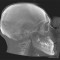

L’Unità Operativa di Radiologia Odontoiatrica, ubicata presso il Dipartimento, è dotata di apparecchiature all’avanguardia nella diagnostica odontostomatologica e del massiccio-facciale. In particolare è presente un’apparecchiatura TC Cone Beam di ultima generazione che consente l’acquisizione volumetrica ad alta definizione ed a bassissima dose dell’intero volume cranio-facciale comprese le articolazioni temporo- mandibolari e le prime vertebre cervicali. Tale esame oggi trova larga applicazione nel campo della diagnostica odontoiatrica e del massiccio facciale, come lo studio pre e post-implantare, la valutazione di elementi dentali inclusi, lo studio di lesioni odontogene e non odontogene, la traumatologia cranio-facciale ed anche la valutazione dei seni paranasali, dell’orecchio e delle articolazioni temporo-mandibolari. Grazie all’acquisizione volumetrica ed alla bassa dose di radiazioni tale metodica è oggi indicata anche nella pianificazione del trattamento ortodontico. Nell’Unità Operativa è inoltre presente l’Orthophos Plus della Sirona Dental System che consente di effettuare esami radiografici standard digitali delle arcate dentarie, dei seni paranasali e delle articolazioni temporomandibolari ed inoltre teleradiografie nelle proiezioni latero-laterale ed antero-posteriore per studio ortodontico. L’Unità Operativa è collegata in rete con i vari reparti della clinica per una rapida consultazione degli esami radiologici.